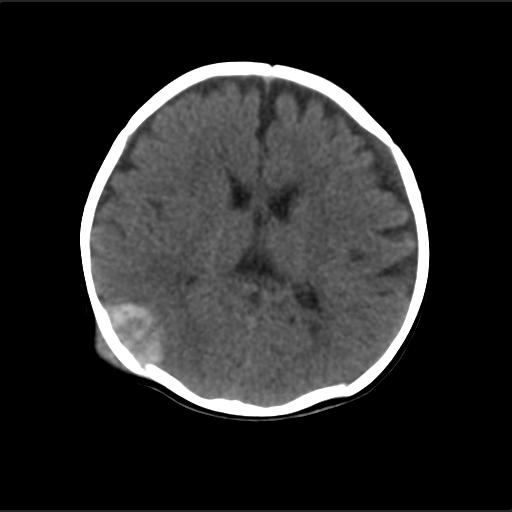

f2m出生已来可见右侧枕部见包块,质地软,无外伤史。包块处ct值16-67hu,大小约3.1x3.2cm左右。

局部颅骨破坏,并以破坏为中心的高密度肿块影,内示软骨影,考虑颅骨软骨瘤.

仔细看颅骨是分离

骨质还算完整。

病灶位于颅缝区,向内外生长,边缘光整。考虑脑膜瘤

血肿机化可能性 比较大,伴双侧额颞顶部硬膜下积液。估计产伤引起